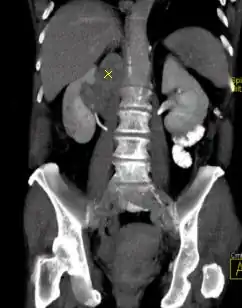

Koronal reformatierte Darstellung von Abdomen und Becken; gut zu erkennen sind u. a. die Leber und die beiden Nieren. -